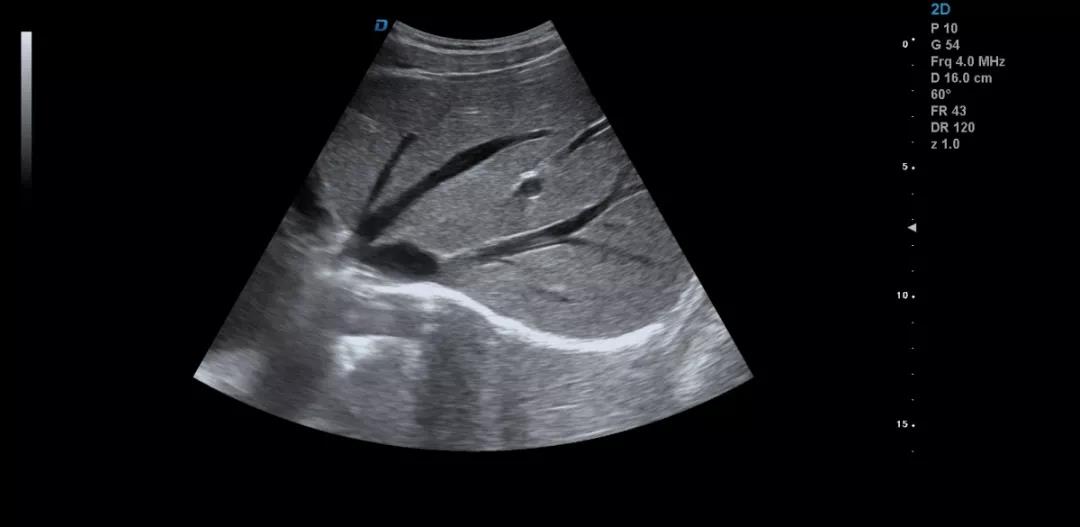

眾所周知,肝臟有很多檢查死角,成為超聲檢查的盲區(qū),如肺和骨所掩蓋處,肝右前上段及右后上段的膈頂部,左外葉外側(cè)角區(qū),沿肝臟表面的肋骨下區(qū)等等部位,只有極其細(xì)致的檢查配上精巧的手法才能盡可能的顯示清楚這些部位。

如果我們能夠細(xì)致的檢查每個(gè)病人,所謂的肝臟死角能夠盡可能的探測(cè)到,肝臟的死角其實(shí)只有膈頂部,其他的部位如果能細(xì)致檢查都可以探測(cè)到。

發(fā)現(xiàn)肝臟病變時(shí)要多切面多角度掃查,可以了解病變的解剖位置并排除假陽(yáng)性。